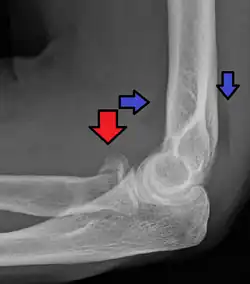

Radial head fracture (red arrow) with posterior and anterior sail sign (blue arrows)

Radial head fractures are diagnosed from a clinical assessment and diagnostic imaging.[7] Symptoms may include pain or tenderness at the radial head, bruising, swelling, and a limited range of motion of the injured elbow.[2] Diagnostic imaging may include ultrasound, plain radiography (x-ray imaging), Computed tomography scan (CT), and magnetic resonance imaging (MRI).[2][4] A fat pad sign may be present on diagnostic imaging and may indicate a radial head fracture.[5]